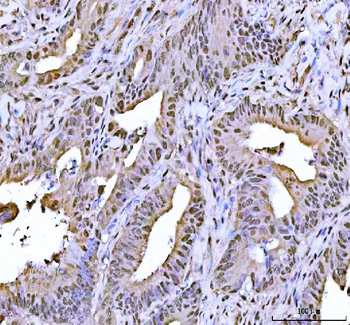

![Anti-FEN1 [SAIC-21C-4]](/images//pub/media/catalog/product/NewWebsite/35/orb1089994_1.png)

![Anti-FEN1 [SAIC-21C-4]](/images/pub/media/catalog/product/NewWebsite/35/orb1089994_2.png)

![Anti-FEN1 [SAIC-21C-4]](/images/pub/media/catalog/product/NewWebsite/35/orb1089994_3.png)